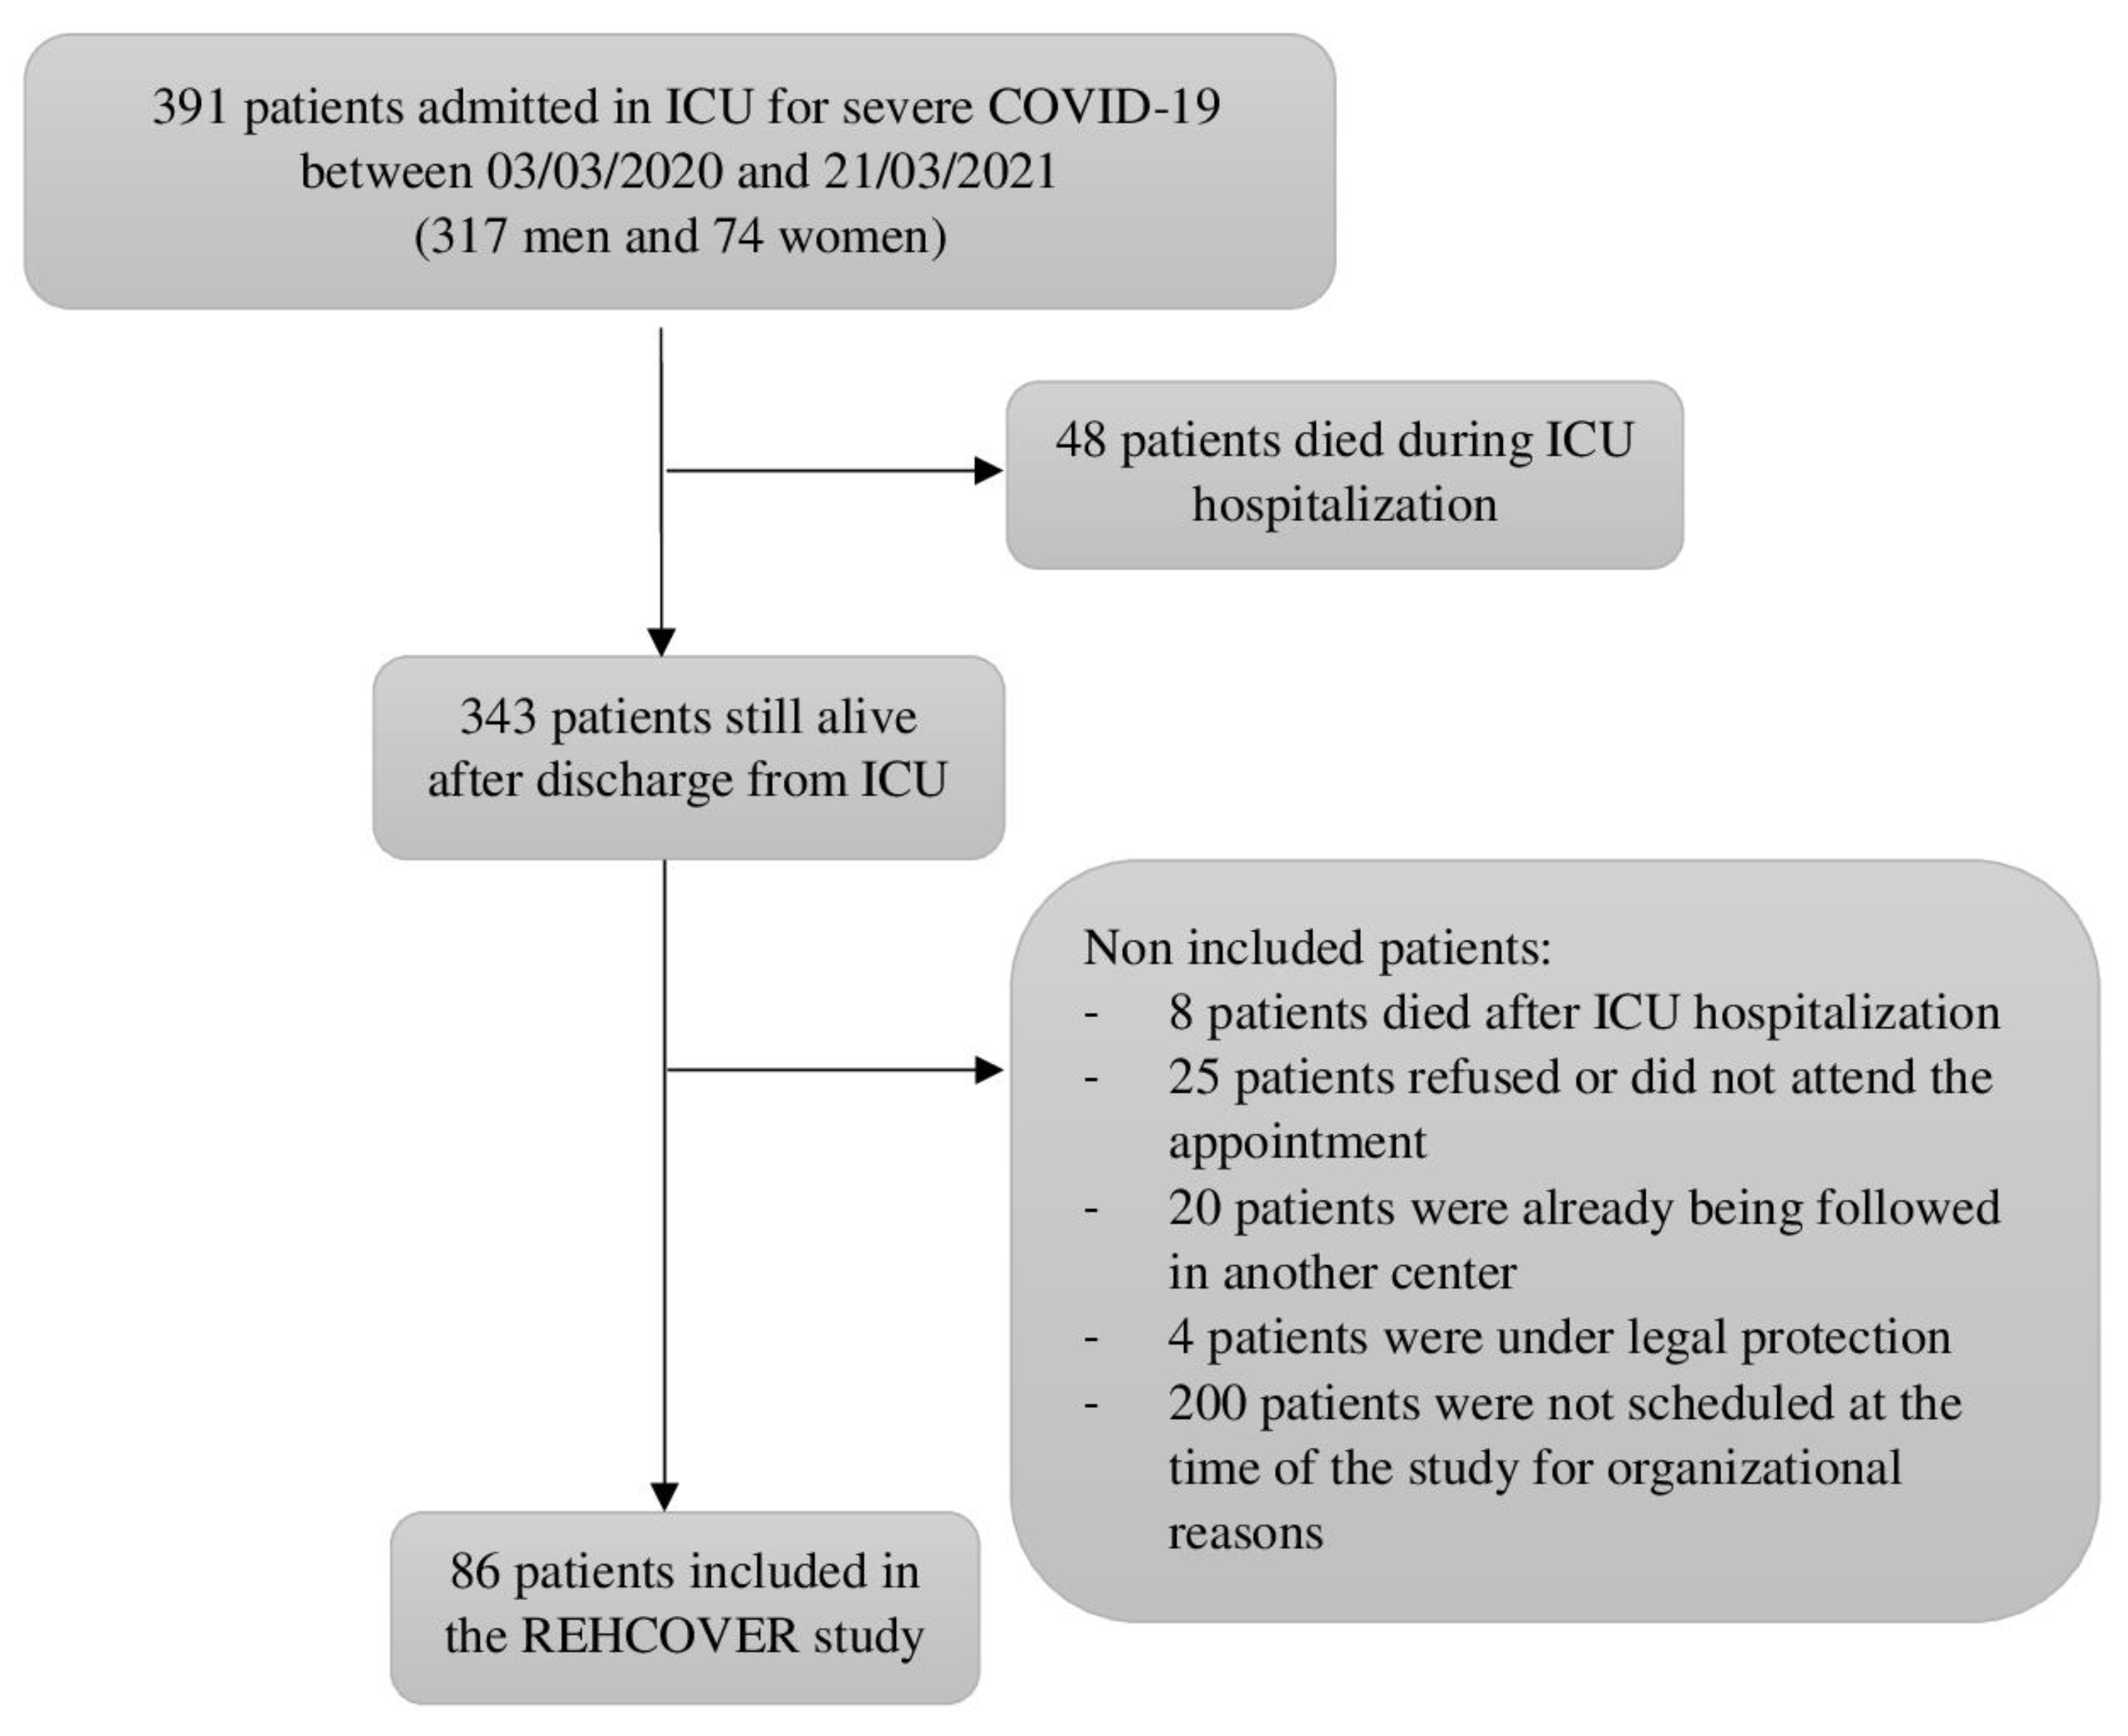

2.1. Population